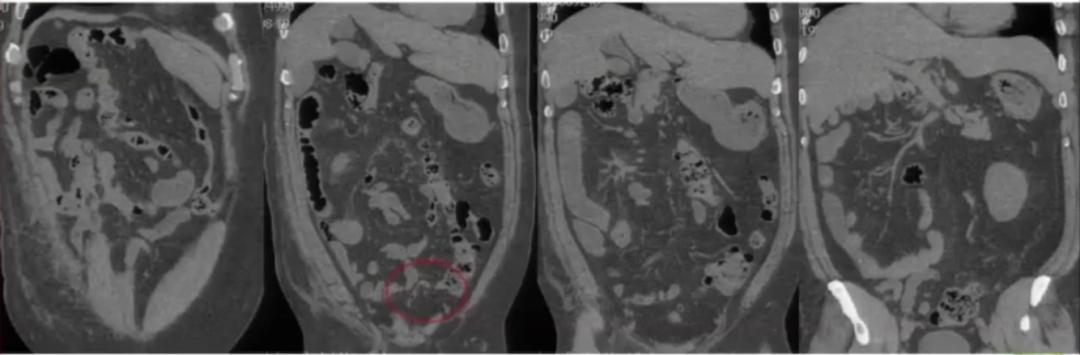

肾癌伴血管结构畸形

肾癌伴血管结构畸形患者的血管结构畸形往往容易被忽视。 在手术的过程中,如不注意就可能造成肝右叶血流的回流障碍,导致严重的临床后果。

中肠旋转不良

中肠旋转不良是指 胚胎第6周,肠袢突入脐腔,以肠系膜上动脉为轴心逆时针90°旋转,第10周时,空肠领先,回肠、盲肠、 升结肠相 继退回体腔,并逆时针180°旋转,第11周末时,盲肠下降至右下腹,中肠系膜与后腹膜融合,将十二指肠,盲肠、升结肠固定在膜腔后方。

先天性肠旋转不良是指胚胎期肠道以肠系膜上动脉为轴心逆时针旋转270°的过程发生障碍,使肠道位置发生异常和肠系膜附着不全的一种先天性畸形。

临床意义:

①多无症状,如出现症状可表现为肠梗阻、反复腹痛、腹胀,可合并肠扭转等严重并发症;

②临床误诊,如合并阑尾炎可导致体征在右上腹或左下腹;

③术前估计不足。

影像表现:

肠管位置异常:根据旋转不良程度,可以表现为回盲部高位,空肠右位、回肠左位等,典型表现为十二指肠水平段未走行至左上腹而折曲向右,小肠位于右腹部,结肠位于左腹部,回盲部及阑尾位于左下腹或盆腔。

肠系膜血管位置异常:肠系膜血管的“换位征”和“漩涡征”。

肠梗阻表现:肠管扩张、积气积液、肠壁增厚等。

案例分享:

图9:右侧腹部未见升结肠影,中腹部偏左见有结肠带肠管,其下端可见阑尾影